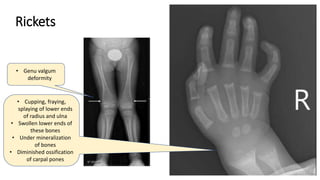

Rickets

• Cupping, fraying,

splaying of lower ends

of radius and ulna

• Swollen lower ends of

these bones

• Under mineralization

of bones

• Diminished ossification

of carpal pones

• Genu valgum

deformity